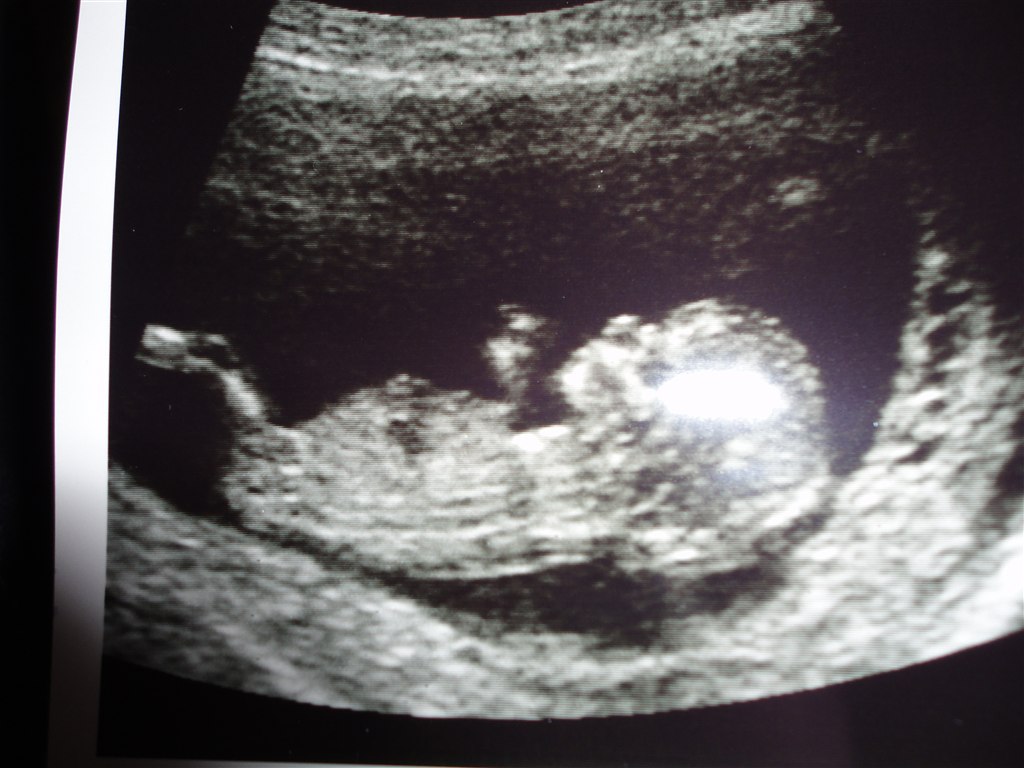

Så var vi til NF idag. Hvor er det vildt at man kan se så meget! Den lille suttede på hænderne

Og var MEGET livlig

Talene hed 1:16.546, så det er vist meget godt